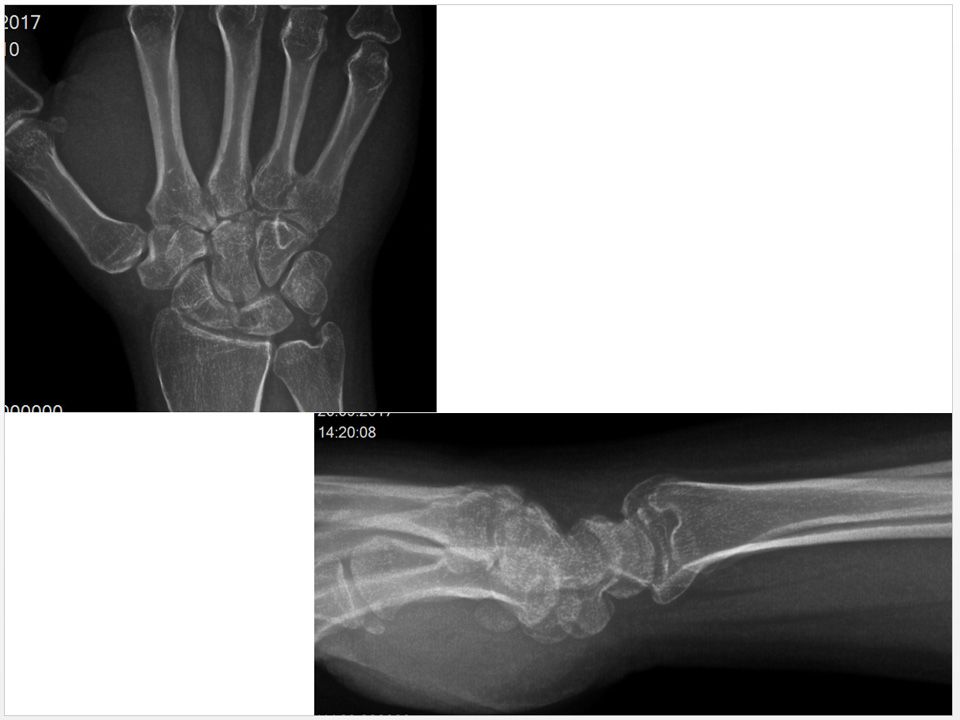

Case 03 - Intraosseous Ganglion Cyst of The Lunate 37 yr, male, furnisher, right hand dominancyLeft wrist pain for 3 yearsTenderness with palpation over lunateLeft wrist flexion 50°, extension 50°